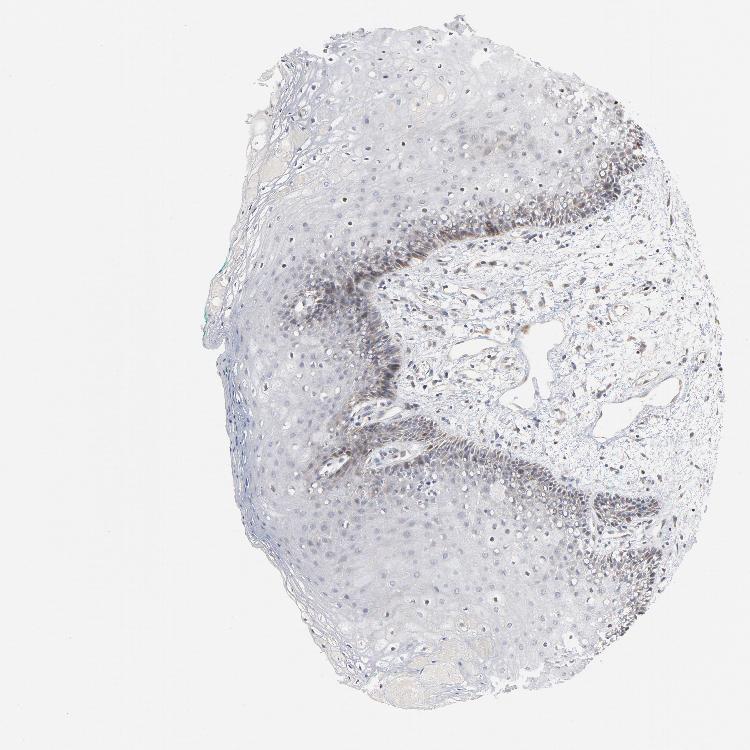

TISSUE PRIMARY DATA ORAL MUCOSA Show tissue menu

Oral mucosa

ORAL MUCOSA - Antibody stainingi

Antibody staining in the annotated cell types in the current human tissue is reported as not detected, low, medium, or high, based on conventional immunohistochemistry profiling in selected tissues. This score is based on the combination of the staining intensity and fraction of stained cells.

Each image is clickable and will lead to virtual microscopy that enables deeper exploration of all samples and also displays staining intensity scores, fraction scores and subcellular localization as well as patient and tissue information for each sample.

Antibody HPA048630Antibody HPA061142Antibody CAB004026

Squamous epithelial cells MediumNot detectedLow